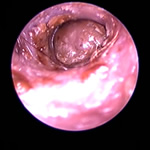

鼓膜とその周囲の病気

角化症、脂漏症という生まれつきの体質を持ったワンちゃんは耳垢が多くなりがちです。また、角化症、脂漏症の長毛種となれば、耳の中に毛が生えた犬種も多く耳道から耳垢を排泄しにくくなります。それらが原因で耳に汚れがたまります。また長毛種はトリミングに行く回数も多く、耳を洗う機会が多くなります。こんな負の連鎖があり、いずれも耳を悪くする大きな原因になります。その全ての要因に対処しなければ耳の病気は解決しません。写真は鼓膜手前に耳垢や毛が蓄積し、通常の耳洗浄ではきれいにできない状態です。セカンドオピニオンで来院されるワンちゃんで最も多い病気の1つです。

フレンチブルドックはアトピー性皮膚炎、食物アレルギー、脂漏症、甲状腺機能低下症など皮膚病になりやすい犬種です。さらにフレンチブルドックの耳道はもともと入口がとても広く、鼓膜手前で極端に狭くなっています。もし、これらの皮膚病を発症すると外耳炎が起こりやすくなります。外耳炎が起こると耳垢が溜まり、耳洗浄による耳道刺激があったり、微生物の増殖など負のサイクルに陥ることがあります。さらに耳道周囲の体毛が耳の中に入りやすいため、鼓膜手前に毛が蓄積します(写真)。体毛、微生物が増殖した耳垢、皮膚病の放置といった悪化因子が重なると非常に重度の中耳炎になります。